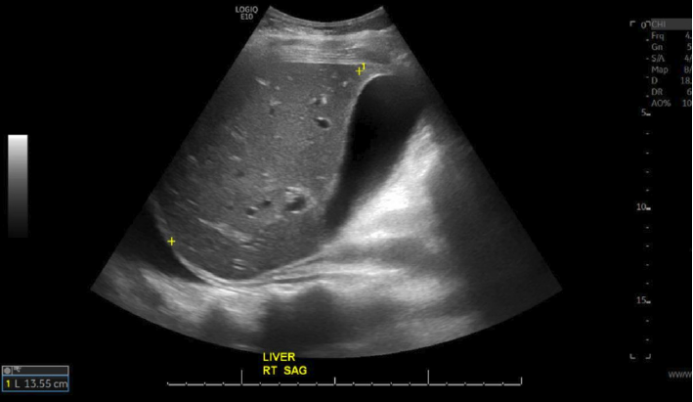

住院第 3 天,行口服造影剂盆腹腔 CT 检查,显示胰头部低密度病灶,大小 3 cm×2 cm×2 cm,不伴导管扩增,远端实质轻度萎缩,怀疑恶性肿瘤(图 2)。

图 2. 腹部 CT 显示胰头占位 [1]